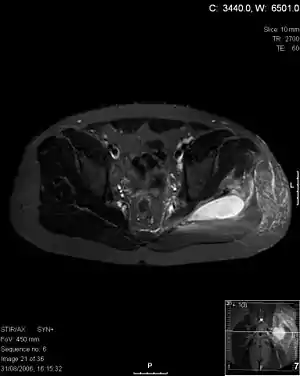

پیومیوزیت یک عفونت حاد چرکزای عضلات - معمولاً ماهیچههای سرینی (گلوتئال)، چهار سر یا ساق - میباشد که اکثراً در مناطق گرمسیری و بهدنبال فعالیت عضلانی شدید ایجاد میشود. شایعترین فرم ماهیچهآماس چرکی، که معمولاً در اثر استافیلوکوک طلائی ایجاد میشود، به آرامی با درد موضعی و بهدنبال آن، تب، تورم و تشکیل آبسه، آغاز میگردد. یک نوع حاد که معمولاً در اثر استرپتوکوک میباشد، میتواند ظرف چند ساعت یا چند روز پیشرفت کند و شبیه عفونت با سازوارههای کلوستریدیایی که تشکیل گاز نمیدهند، میباشد.